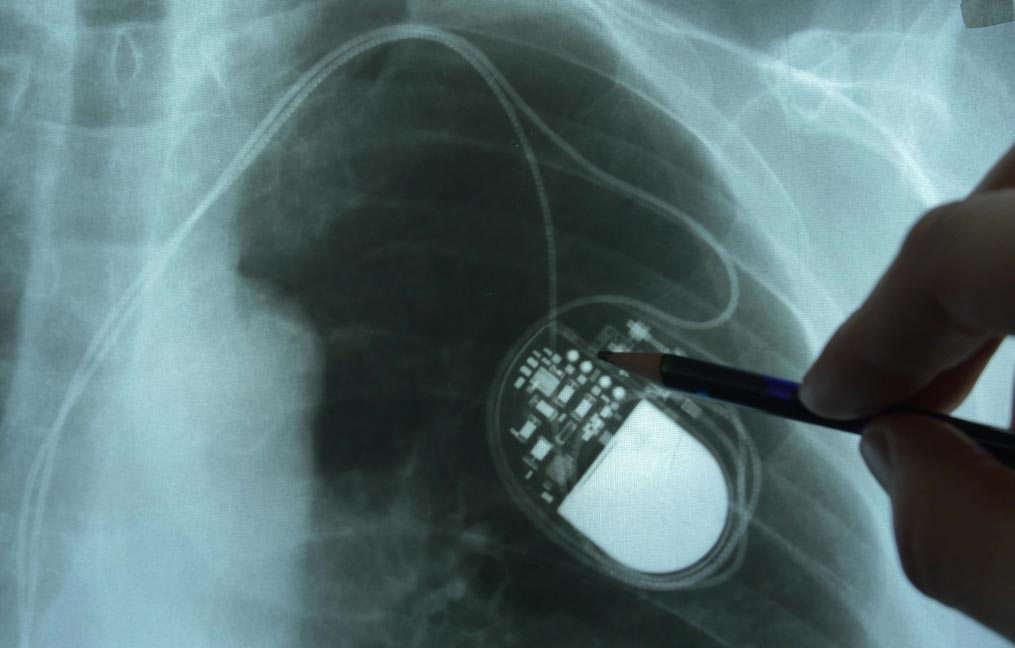

Recycled pacemakers function as well as new devices, international study suggests

Recycled pacemakers can function as well as new devices, a University of Michigan-led study suggests.

These used and reconditioned devices have the potential to increase access to pacemaker therapy in low- and middle-income countries, where many patients cannot afford the treatment.